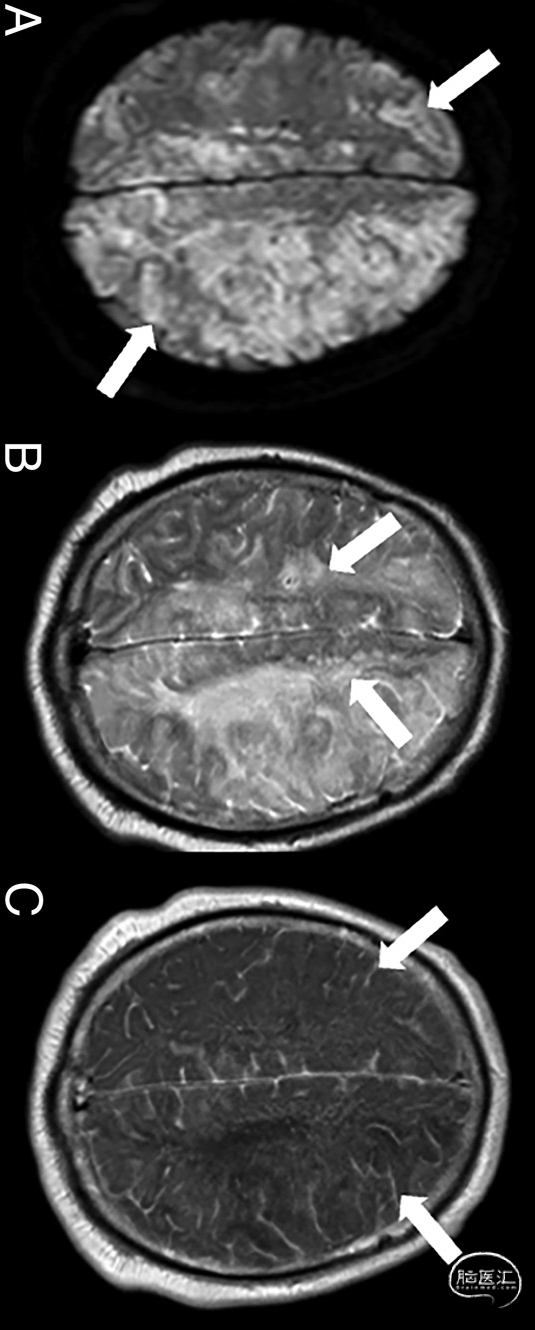

图2.男性,68岁。症状疑似CAE。增强脑MRI显示,远端血管床存在细胞毒性(白色箭头,DWI序列,a)和血管源性水肿(白箭头,T2-FLAIR序列,B)的混合模式,水肿区域附近有伴随软脑膜增强(白色箭头、增强后[MultiHance;Bracco Diagnostic]2D自旋回波T1序列,C)。头颈部CTA显示纵隔积气,食管和左心房之间有气体(未提供)。这些发现与心脏消融术后心房食管瘘的急性空气栓塞一致: